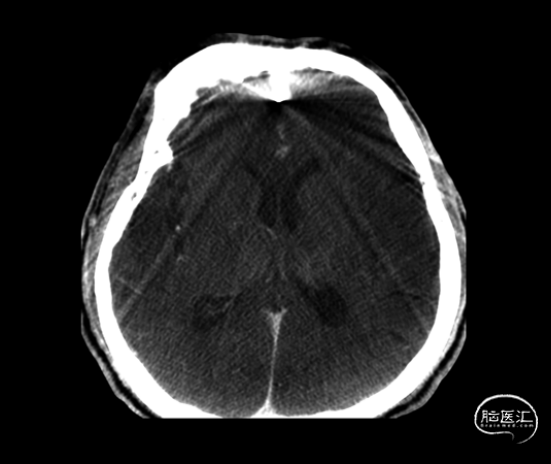

栓塞术后即刻CT未见颅内出血、Onyx胶逃逸或异位栓塞(图6)。次日,患者未诉明显不适,查体无新发神经系统体征。术后第二日,患者顺利出院。

图6. 术毕即刻CT。